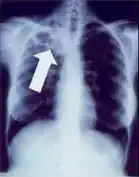

-

Dense homogenous opacity in right, middle and lower lobe of primary pulmonary TB. -